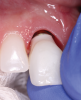

(5.) The tissue at the site of tooth No. 8 has been conditioned and is ready for delivery of the final crown.

Figure 5